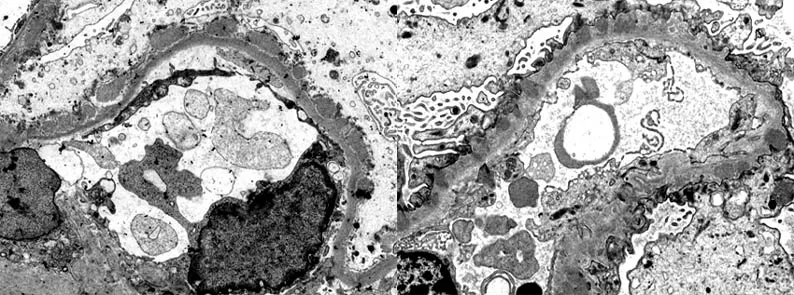

- Biopsy: Normal on light microscopy; EM shows effacement of podocyte foot processes.

- Gold Standard: Kidney Biopsy (Light, Immunofluorescence, & Electron Microscopy).